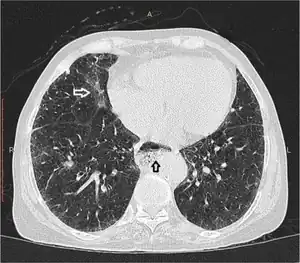

Esophageal dysmotility black arrow | |